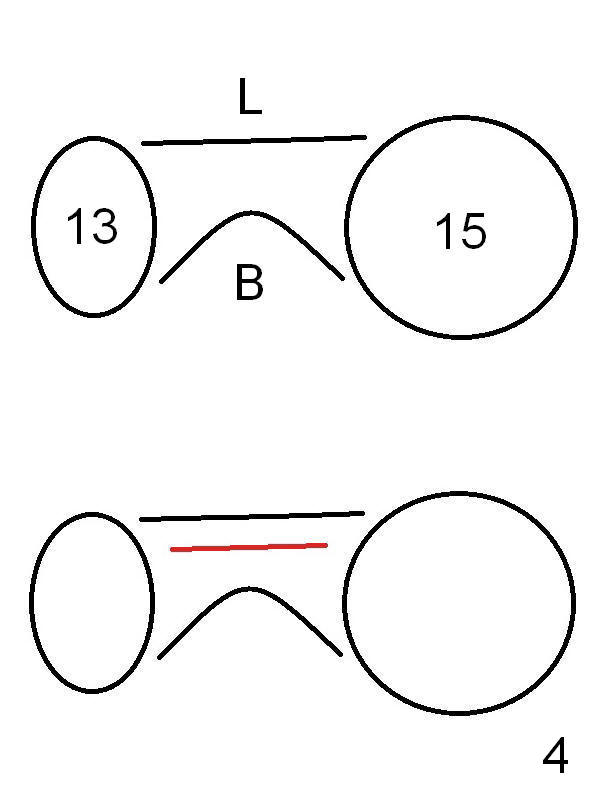

The tooth #14 of a 52-year-old lady had severe bone resorption 6 years ago (Fig.1 (red dashed line: sinus floor)). The bone resorption persists after the tooth exfoliated (Fig.2). Clinically, the buccal plate (Fig.4 (occlusal view) upper panel: B) is concave (take preop photos). #15 scalpel will be used for incision (red line in Fig.4 lower panel, near the lingual plate (L)) and initiation of bone expansion. The latter is followed by bone scalpels, bone blades and RTs at the depth of 14 mm. A 4.5x17 mm Tatum tapered tap is used for 14 mm. PA is taken. If the bone is dense, the depth is less than 14 mm in bone. Use RT2,3 to reach 17 mm. A 5x14 mm bone-level implant is placed (Fig.3). Crown cementation will be done for the tooth #3 before surgery.